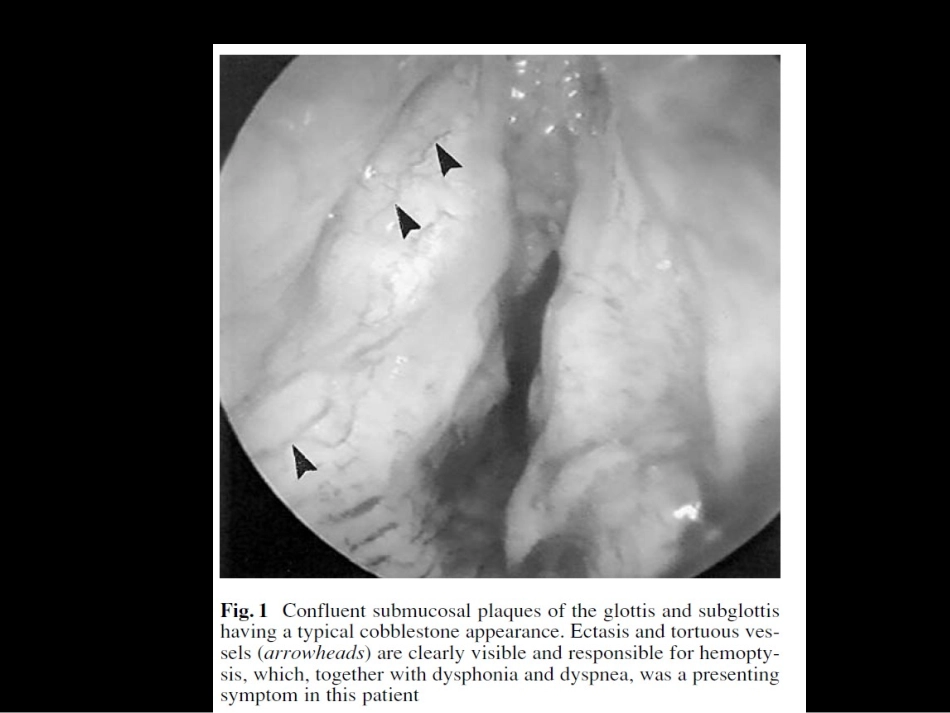

Laryngo-tracheobronchialamyloidosis喉、气管、支气管淀粉样变•amyloidosisisusuallyalocalizedphenomenonthatisrarelyassociatedwithsystemicinvolvement.•Hoarsenessisthemostcommonpresentingsymptom.•Clinicalfindingsatlaryngoscopyarevariable,nonspecific,anddifficulttodistinguishclinicallyfromotherlaryngeallesions.•Thediagnosisisrevealedbypathologicexaminationoftissuesamples.•Traditionally,treatmenthasincludedpartialortotalsurgicalexcisiontomaintainafunctionallaryngealairwayandoptimizevoice.•淀粉样变性是一组蛋白质以异常的纤维结构沉积于细胞之间,该类纤维接触硫和碘会出现和淀粉一样的反应,故命名为淀粉样变性普通光镜:心肌纤维之间有不定形的浅红色沉淀物淀粉样蛋白的特征刚果红染色:淀粉样物质经染色后应为橙红色,偏振光下,淀粉样物质为“苹果绿”双折•免疫荧光:κ轻链蛋白阳性,λ轻链蛋白阳性•免疫电镜检测免疫电镜可见显示轻链沉积的胶体金颗粒特异定位于淀粉样纤维部位,每个病例均被单一品种轻链蛋白(κ或λ)标记•电镜:纤细、不分枝、僵直的纤维原发性,继发性•原发性淀粉样变主要是由循环血液中免疫球蛋白的轻链及其碎片沉积于组织器官而引起,常累及心脏、肾脏、血管壁、胃肠道、舌及呼吸道,以心、肾最多见,大多数累及1,2个器官•继发性淀粉样变常继发于结核、梅毒、慢性肾病、结缔组织疾病、肿瘤等基础疾病系统性,局限性•Insystemicamyloidosistheamyloidfibrilproteinistypicallyproducedatdistantsitesandcarriedinthebloodstreamwithdepositionatmultiplesites,•inlocalizedamyloidosistheproteinistypicallydepositedatthesiteofproductionandnottransportedinthebloodstream.本文回顾分析了1998年11月至2008年10月间在我院诊治的34例原发性呼吸系统淀粉样变性患者的临床资料,并结合文献复习,分类及及临床表现•临床上将呼吸系统淀粉样变性分为4型:•①上呼吸道淀粉样变其中喉是最常见部位,主要的表现是声音嘶哑,可伴有刺激性咳嗽,病变广泛者可引起呼吸困难,甚至窒息CT上见喉部声带增厚,喉室消失,声门下区有软组织肿物影。喉淀粉样变性在MRI上表现为与骨骼肌类似的信号,这有利于和喉部肿瘤(与骨骼肌的信号不同)鉴别•②气管、支气管淀粉样变分为局灶性和弥漫性,主要症状有咳嗽、咯血、呼吸困难、喘鸣、声音嘶哑,常继发感染。气管、支气管淀粉样变的胸片多表现为肺纹理增强,也有部分患者胸片无异常表现,由于管腔狭窄,故可出现阻塞性炎症、肺不张、局限性或广泛性肺气肿。CT扫描可见气管、支气管管腔狭窄,管壁不规则增厚,在黏膜下可见线条状钙化影(为气管、支气管特征意义的影像学表现)。T1WI显示淀粉样变性的气管、支气管管内外壁呈凹凸不平的隆起,信号为中等偏高;在T2WI上呈低或等低信号,而炎症和肿瘤在T2WI上普遍呈现为高信号,故MRI比CT在诊断呼吸道淀粉样变性中更具有特异性。气管支气管淀粉样变性的肺功能检查为阻塞性肺通气功能障碍•③肺淀粉样变可分为结节性和肺泡间隔弥漫性淀粉样变,主要症状有反复的咳嗽、咳痰、咯血、气促,肺结节性淀粉样变表现为肺内单发或多发结节,这种类型较少累及其他器官。肺泡间隔弥漫型最少见,但容易导致呼吸衰竭。肺淀粉样变多在影像检查时发现,胸片上为两肺弥漫性不均匀的纹理增强、斑点、细小结节或斑片影,偶有胸水;高分辨CT可见小叶间隔增厚呈网状和(或)弥漫分布的直径0.5~5mm的边界清晰小结节,以两肺下叶多发,偶见点状或细环状钙化。肺功能检查表现为正常或弥散功能障碍和限制性通气功能障碍。•④纵隔型该型多见于系统性淀粉样变,平片上主要表现为肺门、纵隔结节状密度影或融合为结节状团块,内可有蛋壳状或不规则状钙化,CT上更为明显诊断:•由于呼吸系统淀粉样变可为局限性淀粉样变,也可为系统性淀粉样变受累的器官之一,而这两种不同的分类有不同的治疗和预后,因此在临床上对于确诊为淀粉样变的患者,首先要判断是全身性还是局限性淀粉样变,应对患者进行血、尿常规,血沉、肝功、肾功、蛋白电泳、血清免疫学测定、心电•图、胸部X线摄片,以排除淀粉样变的系统侵犯。必要...